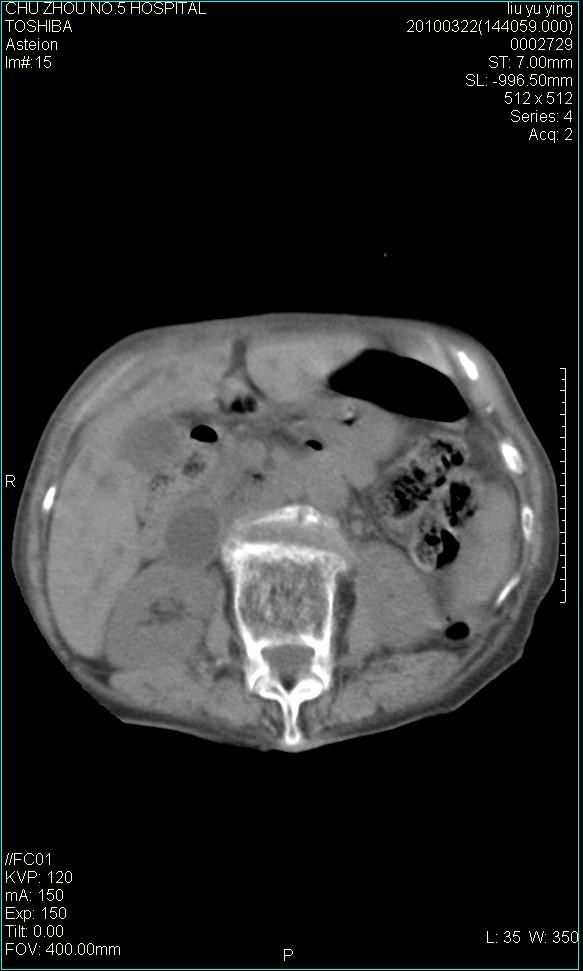

以下是引用科室第一人在2010-3-23 6:50:00的发言:[br]胆总管下段梗阻,多为肿瘤性病变,巨形胆囊,胆囊炎胆囊窝积液。[br]双侧胸腔积液,右降

以下是引用随光逐影在2010-3-23 8:12:00的发言:[br]1)胆系低位梗阻(肝内外胆管扩张,胆囊增大),原因待查。2)胆囊炎。3)双侧少量胸腔积液。4)降主动脉迂曲。